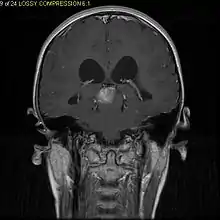

Pilocytic astrocytoma (and its variant pilomyxoid astrocytoma) is a brain tumor that occurs most commonly in children and young adults (in the first 20 years of life). They usually arise in the cerebellum, near the brainstem, in the hypothalamic region, or the optic chiasm, but they may occur in any area where astrocytes are present, including the cerebral hemispheres and the spinal cord. These tumors are usually slow growing and benign, corresponding to WHO malignancy grade 1.[1]

Usually – depending on the interview of the patient and after a clinical exam which includes a neurological exam and an ophthalmological exam – a CT scan and/or an MRI scan will be performed to confirm the presence of a tumor. They are usually easily distinguishable from normal brain structures using these imaging techniques. A special dye may be injected into a vein before these scans to provide contrast and make tumors easier to identify. Pilocytic astrocytomas are typically clearly visible on such scans, but it is often difficult to say based on imaging alone what type of tumor is present.

Pilocytic astrocytomas are often cystic tumors, and, if solid, tend to be well-circumscribed.